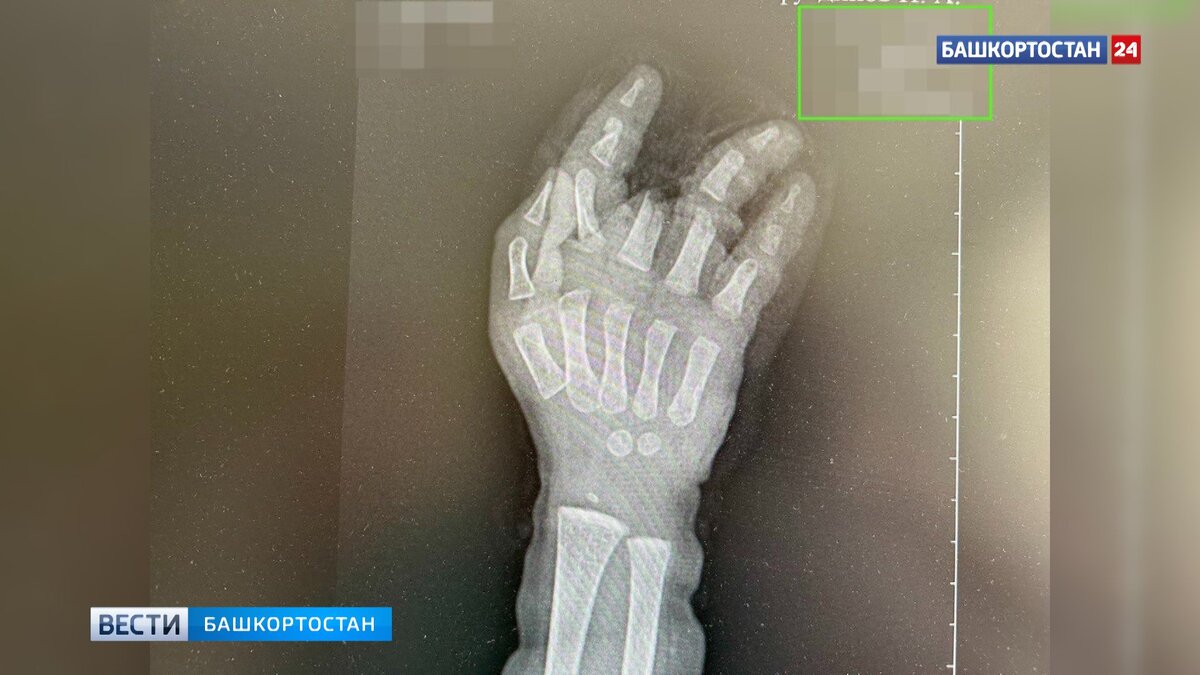

Малыш едва не лишился пальцев, предстоит серьезная операция. В Башкирии годовалый ребенок получил тяжелые травмы, засунув руку в электромясорубку. Бригадой скорой помощи малыша экстренно госпитализировали в районную больницу. Ребенок засунул левую руку в работающую мясорубку, когда мама отвлеклась на несколько минут. Маленького пациента срочно доставили в центральную районную больницу, где оказали первую помощь. Руку извлекали из мясорубки под внутривенным наркозом. "Для дальнейшего лечения, ребенка направили в городскую детскую клиническую больницу №17. Травматологи-ортопеды провели ревизию раны, наложили гипсовую лангету. Малышу планируется реконструктивная пластика кисти руки", — сообщили в Уфимской ГКБ № 17. Как рассказали "Вести-Башкортостан" в пресс-службе Минздрава РБ, сейчас ребенок находится в больнице в состоянии средней степени тяжести. На следующей неделе медики планируют провести операцию.

Ребенок засунул левую руку в работающую мясорубку, когда мама отвлеклась на несколько минут. Маленького пациента срочно доставили в центральную районную больницу, где оказали первую помощь. Руку извлекали из мясорубки под внутривенным наркозом.

"Для дальнейшего лечения, ребенка направили в городскую детскую клиническую больницу №17. Травматологи-ортопеды провели ревизию раны, наложили гипсовую лангету. Малышу планируется реконструктивная пластика кисти руки", — сообщили в Уфимской ГКБ № 17.